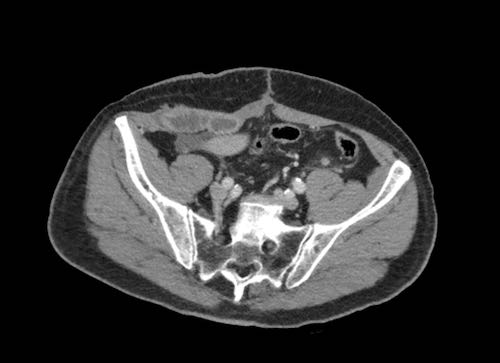

Cuộn xem ảnh CT

Ca lâm sàng 1

Cuộn qua các lát cắt.

Bạn có thể phát hiện tất cả các tổn thương cấy ghép phúc mạc không?

Bệnh nhân này đã được phẫu thuật và toàn bộ phúc mạc được ghi nhận phủ kín bởi các tổn thương u dạng kê.